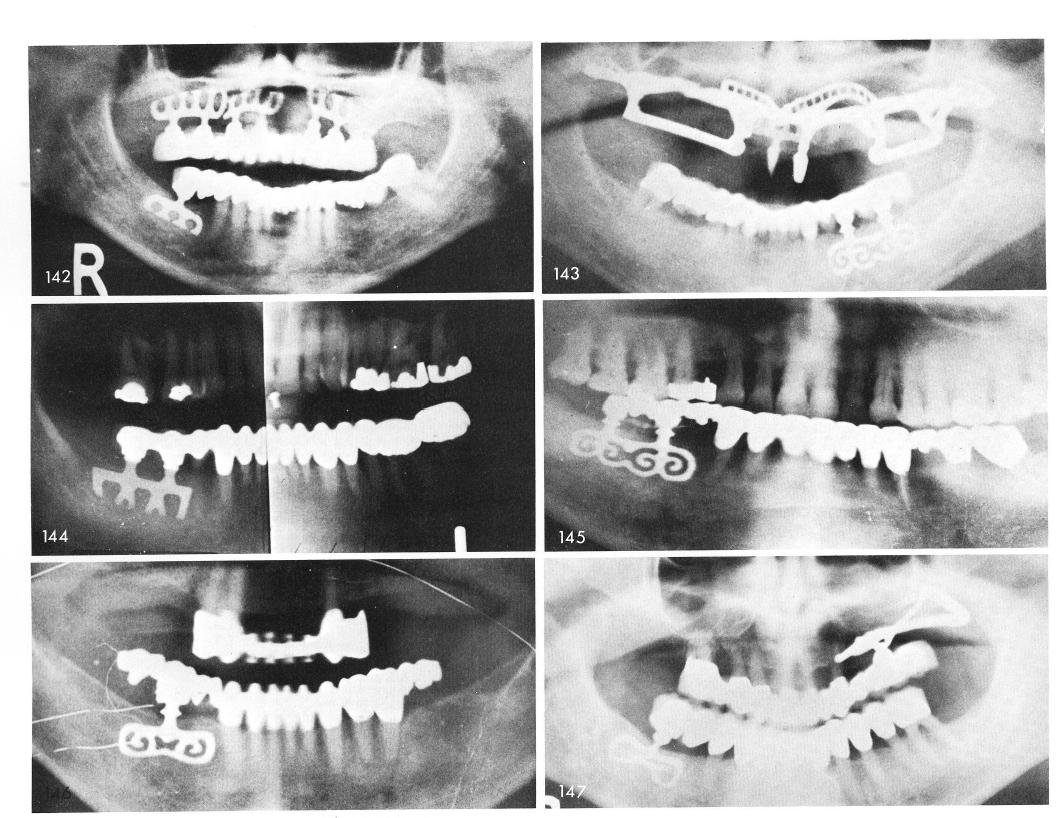

Mandibular Implants (published 1977)   Dr. Leonard I. Linkow